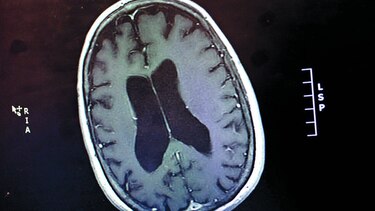

El volumen cerebral de la persona con alzheimer disminuye porque las neuronas dejan de conectarse entre sí. Es decir, la “plasticidad” neuronal disminuye, muere.

En la fase clínica ya hay una muerte cerebral y la única forma de poder hacer un diagnóstico definitivo es con una autopsia del cerebro.